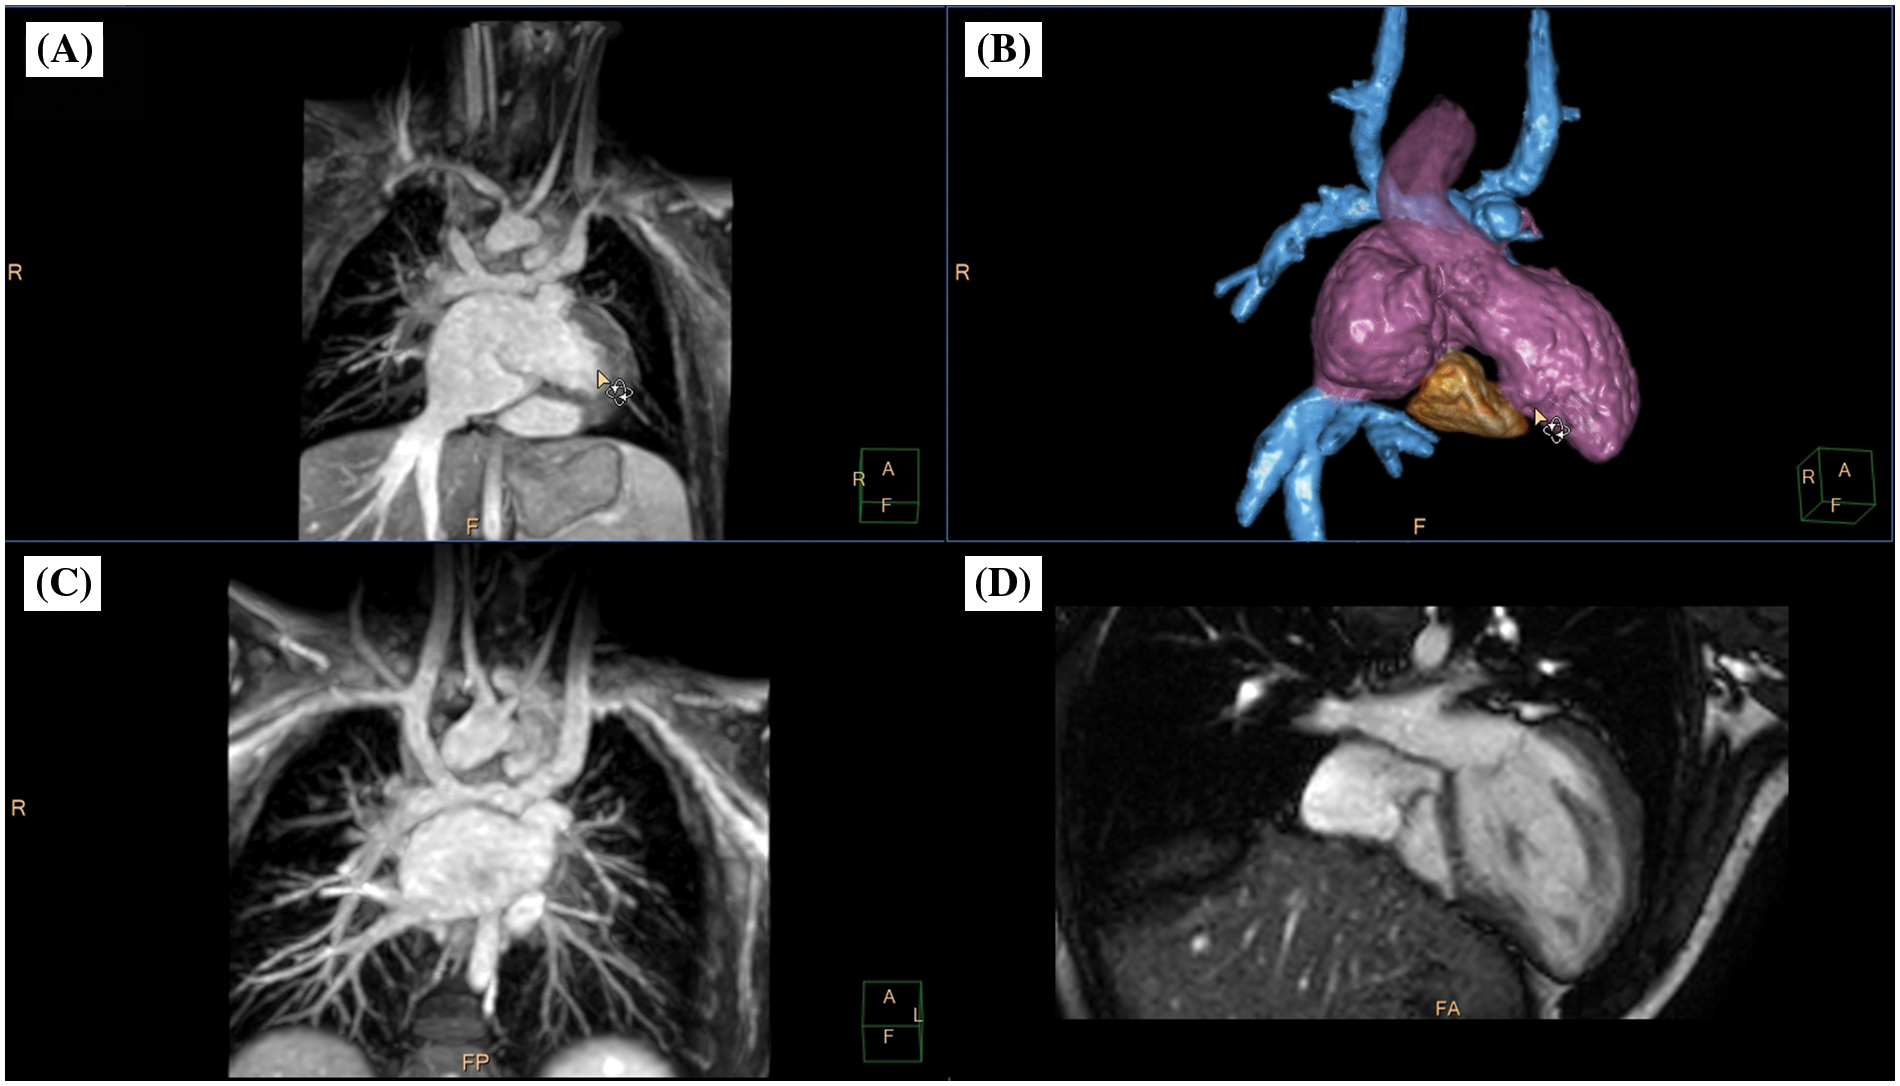

Figure 5: Clinical case example III. (A) Animated angulated volume-intensity projection of the nsWHcs dataset; (B) composite volumetric surface rendering of vascular compartments/endoluminal cavities including inferior vena cava and bilateral Glenn anatomy (blue), atria/single ventricle (violet), ascending aorta (transparent violet) and tricuspid annulus/rudimentary right-ventricular cavity (brown); (C) multiplanar-reformatted projectional view of bilateral Glenn anatomy (angulated coronal geometry); (D) cine imaging of an adjusted 4-chamber geometry depicting tricuspid valve/right-ventricular cavity. Please refer to video 3 for a fully animated case presentation

Video 3 (.MP4 file)

Clinical case example III (same case as shown in Fig. 5)

A 5-year-old boy (bodyweight, 14 kg; heart rate, 85/min; propofol sedation) with a single ventricle (hypoplastic right heart syndrome) after bilateral bidirectional Glenn procedure was scheduled for radiofrequency ablation of an accessory pathway prior to finalizing staged palliative surgery leading to total cavopulmonary connection. Preinterventional CMR imaging identified “supero-inferior ventricle” anatomy with tricuspid annulus and contractile, rudimentary right-ventricular cavity [25]. On subsequent invasive electrophysiological testing, atriofascicular pathway tachycardia (“Mahaim”) was identified and successful radiofrequency ablation performed at the lateral tricuspid valve annulus and neighboring myocardium of the rudimentary right ventricle.